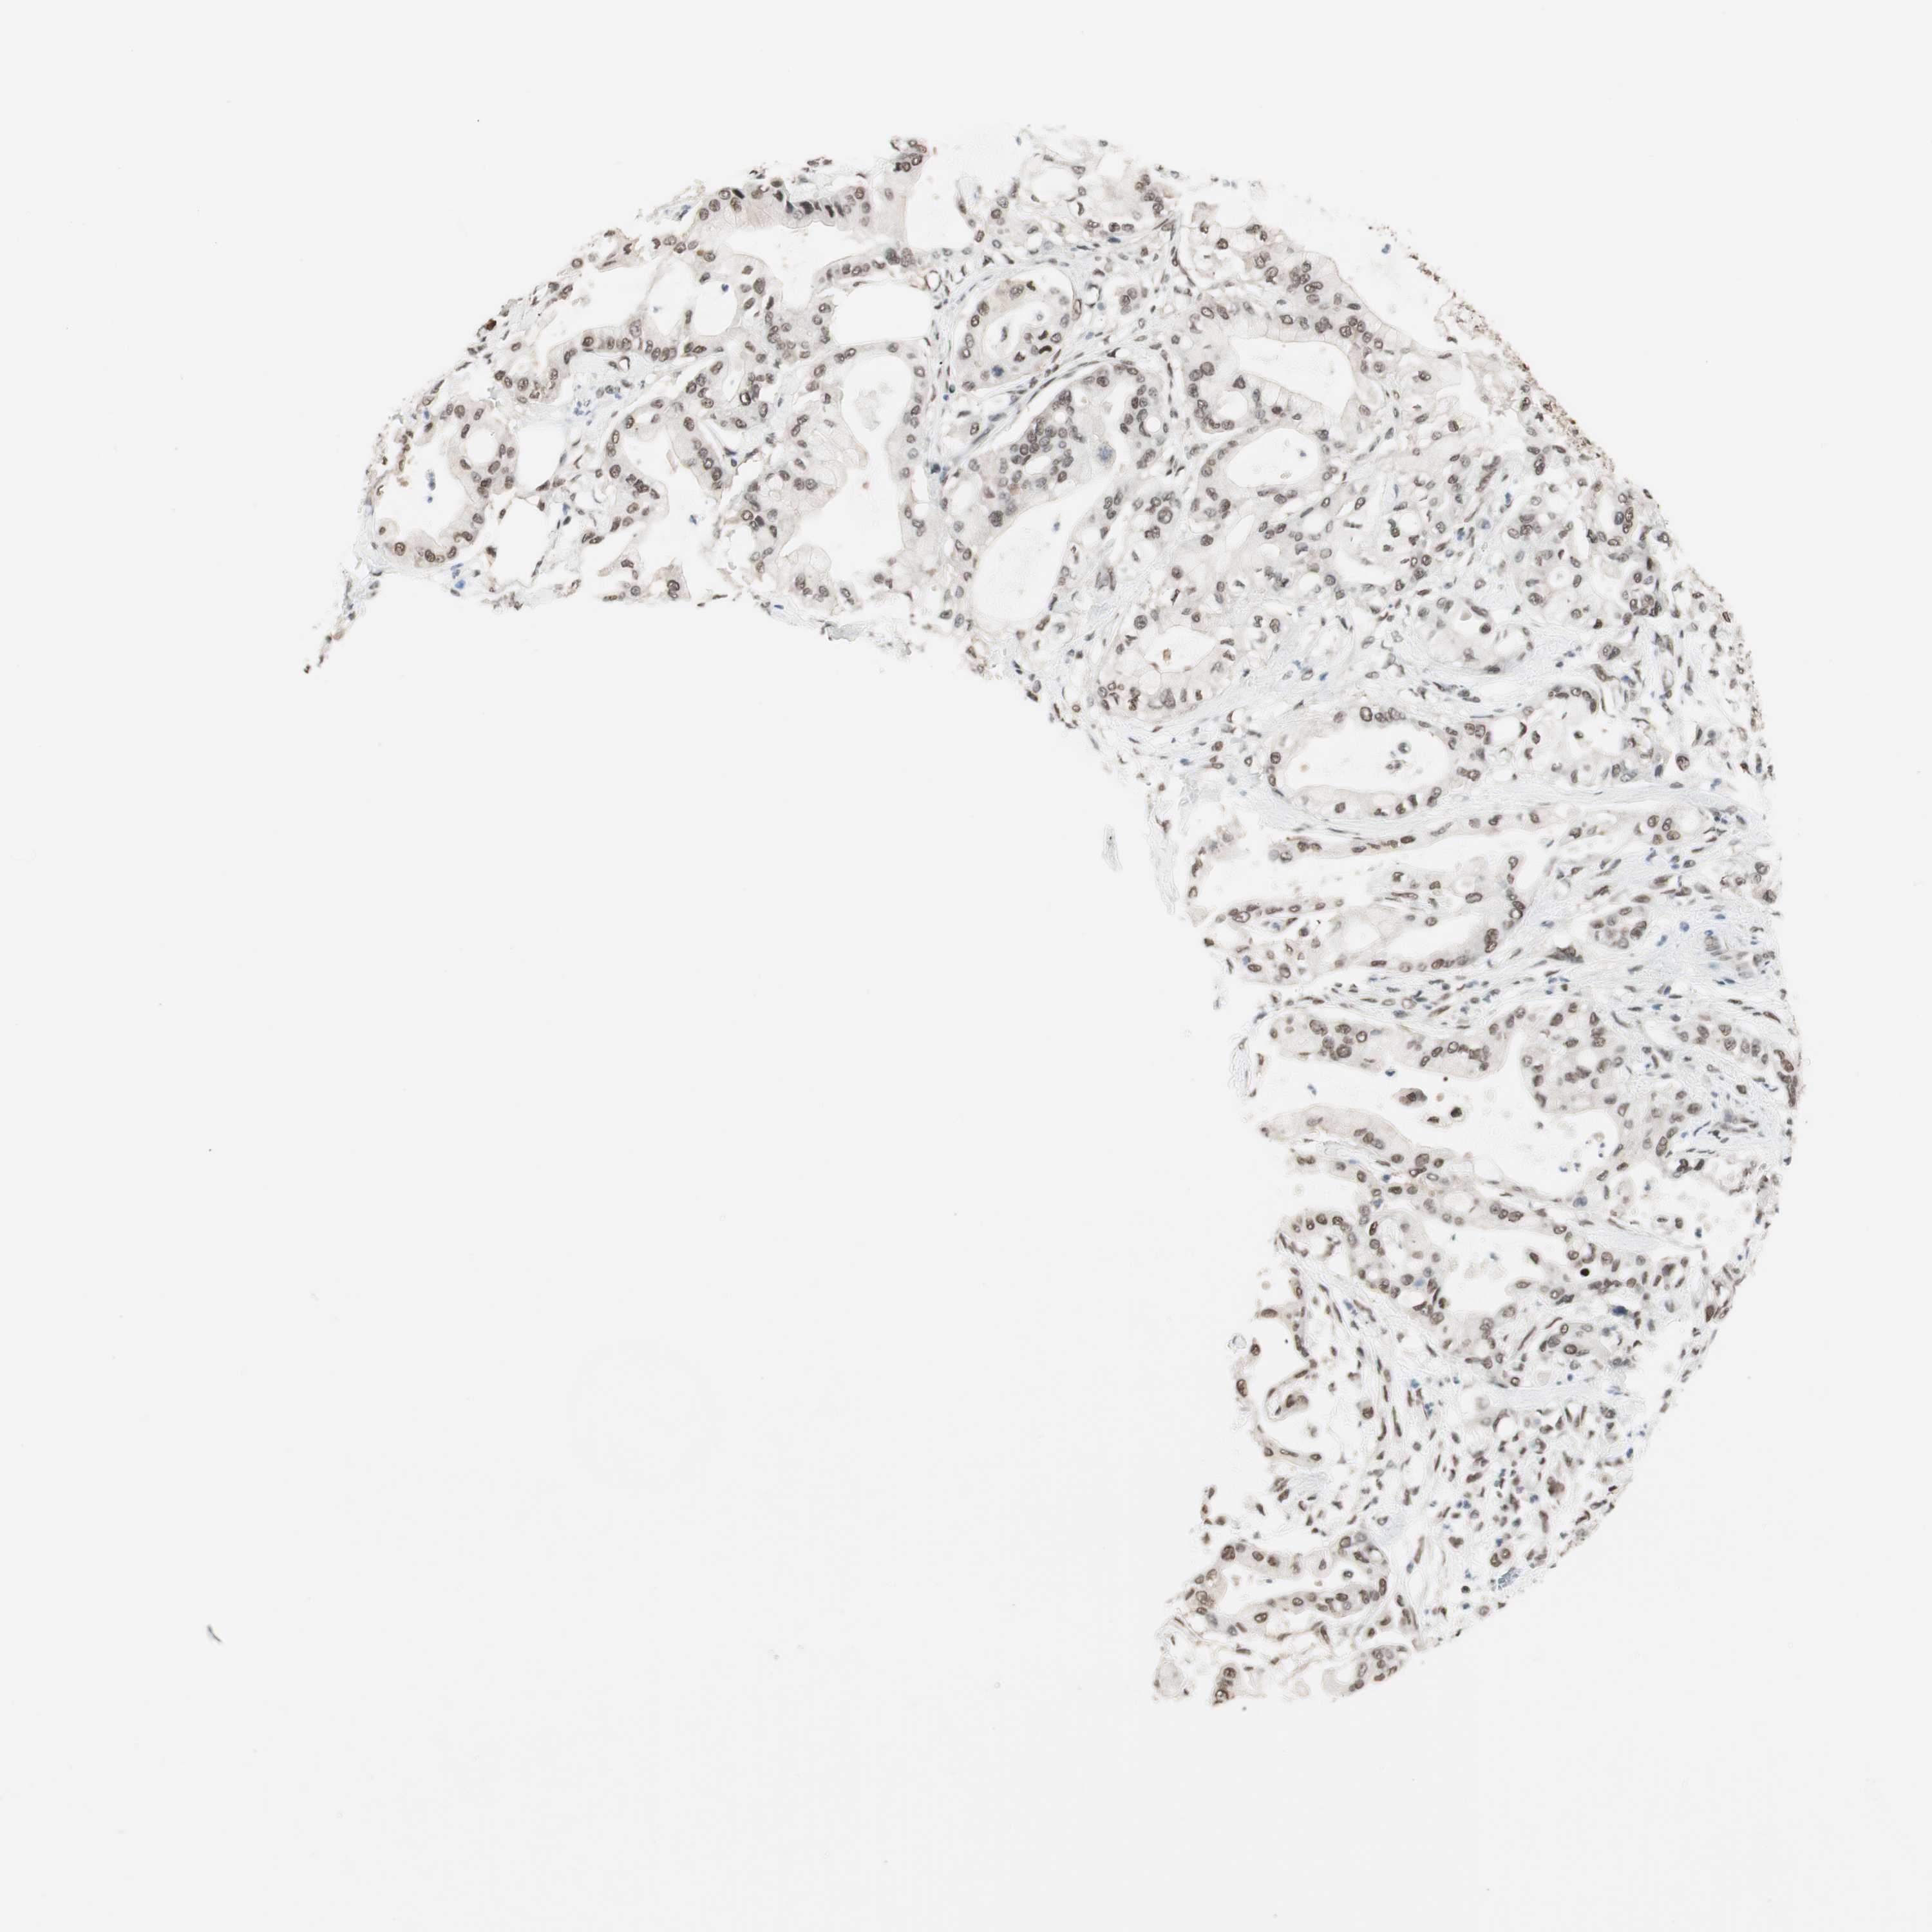

PANCREATIC CANCER - Protein expressioni

A mouse-over function shows sample information and annotation data. Click on an image to view it in a full screen mode. Samples can be filtered based on level of antibody staining by selecting one or several of the following categories: high, medium, low and not detected. The assay and annotation is described here.

Note that samples used for immunohistochemistry by the Human Protein Atlas do not correspond to samples in the TCGA dataset.

Antibody stainingi

Antibody staining in the annotated cell types in the current human tissue is reported as not detected, low, medium, or high, based on conventional immunohistochemistry profiling in selected tissues. This score is based on the combination of the staining intensity and fraction of stained cells.

Each image is clickable and will lead to virtual microscopy that enables deeper exploration of all samples and also displays staining intensity scores, fraction scores and subcellular localization as well as patient and tissue information for each sample.

Antibody HPA003916

Antibody CAB037318

Staining

High

Medium

Low

Not detected

Intensity

Strong

Moderate

Weak

Negative

Quantity

>75%

75%-25%

<25%

None

Location

Nuclear

Cytoplasmic/membranous

Cytoplasmic/membranous,nuclear

Adenocarcinoma, NOS

Adenocarcinoma, metastatic, NOS